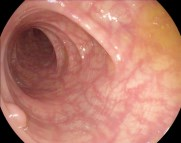

Vision foundation models like the Segment Anything Model (SAM), pretrained on large-scale natural image datasets, often struggle in medical image segmentation due to a lack of domain-specific adaptation. In clinical practice, fine-tuning such models efficiently for medical downstream tasks with minimal resource demands, while maintaining strong performance, is challenging. To address these issues, we propose BALR-SAM, a boundary-aware low-rank adaptation framework that enhances SAM for medical imaging. It combines three tailored components: (1) a Complementary Detail Enhancement Network (CDEN) using depthwise separable convolutions and multi-scale fusion to capture boundary-sensitive features essential for accurate segmentation; (2) low-rank adapters integrated into SAM's Vision Transformer blocks to optimize feature representation and attention for medical contexts, while simultaneously significantly reducing the parameter space; and (3) a low-rank tensor attention mechanism in the mask decoder, cutting memory usage by 75% and boosting inference speed. Experiments on standard medical segmentation datasets show that BALR-SAM, without requiring prompts, outperforms several state-of-the-art (SOTA) methods, including fully fine-tuned MedSAM, while updating just 1.8% (11.7M) of its parameters.